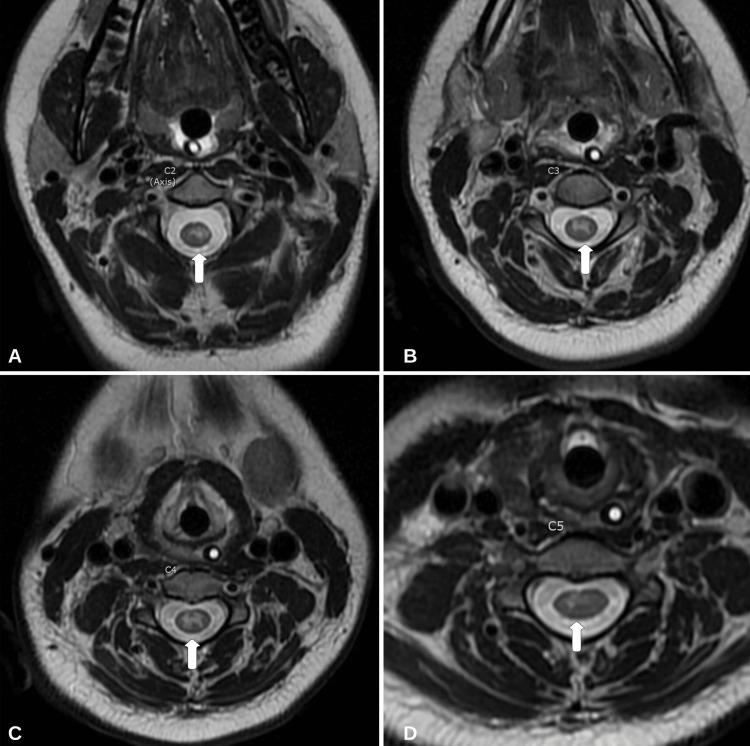

Mild encephalopathy/encephalitis with a reversible splenial lesion (MERS) and longitudinally extensive transverse myelitis (LETM) are neuroinflammatory conditions related to the brain and spinal cord, respectively. Most cases of MERS and LETM are related to a secondary autoimmune process in response to an initial insult (i.e., infection, immunization, etc.). The case of an 18-year-old female who developed a three-day history of fever, quadriplegia, cough, and mild encephalopathy is reported here. The patient tested positive for influenza B by nasopharyngeal swab with polymerase chain reaction (PCR). Initial magnetic resonance imaging (MRI) revealed the presence of a diffusion-restricted non-enhancing lesion confined to the splenium of the corpus callosum (MERS type I) and longitudinally extensive non-enhancing T2 hyperintensities from C1 to C5. The patient was managed with a five-day course of 1,000 mg of intravenous methylprednisolone (IVMP). Additionally, five days of therapeutic plasmapheresis (PLEX) was completed. The patient showed significant improvement with medical management and physical therapy. At the one-year follow-up, her motor symptoms had resolved and endorsed only mild paresthesia in the upper extremities. A repeat MRI revealed a reversal of the splenium lesion and moderate improvement in T2 hyperintensities of the cervical cord. Assessing neuroinvasion of the influenza virus is difficult, and diagnostic challenges arise in determining primary infectious versus autoimmune-mediated neuroinflammation. A review of the literature on influenza infection with radiographic findings of MERS and LETM is included.

伴有可逆性胼胝体压部病变的轻度脑病/脑炎(MERS)和纵向广泛横贯性脊髓炎(LETM)分别是与脑和脊髓相关的神经炎症性疾病。大多数MERS和LETM病例与对初始损伤(即感染、免疫接种等)的继发性自身免疫过程有关。本文报告了一名18岁女性的病例,该患者出现了为期三天的发热、四肢瘫痪、咳嗽和轻度脑病症状。患者经鼻咽拭子聚合酶链反应(PCR)检测乙型流感呈阳性。初始磁共振成像(MRI)显示胼胝体压部存在一个扩散受限的无强化病变(I型MERS),以及从C1到C5的纵向广泛无强化T2高信号。患者接受了为期五天的1000毫克静脉注射甲泼尼龙(IVMP)治疗。此外,还完成了五天的治疗性血浆置换(PLEX)。患者在药物治疗和物理治疗后有显著改善。在一年的随访中,她的运动症状已消失,仅上肢有轻度感觉异常。复查MRI显示胼胝体压部病变逆转,颈髓T2高信号中度改善。评估流感病毒的神经侵袭很困难,在确定原发性感染与自身免疫介导的神经炎症方面存在诊断挑战。本文还对流感感染伴MERS和LETM影像学表现的文献进行了综述。